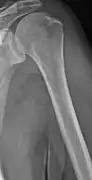

The diagnostic examination of a person with suspected multiple myeloma typically includes a skeletal survey. This is a series of X-rays of the skull, axial skeleton, and proximal long bones. Myeloma activity sometimes appears as "lytic lesions" (with local disappearance of normal bone due to resorption) or as "punched-out lesions" on the skull X-ray ("raindrop skull"). Lesions may also be sclerotic, which is seen as radiodense.[64] Overall, the radiodensity of myeloma is between −30 and 120 Hounsfield units (HU).[65] Magnetic resonance imaging is more sensitive than simple X-rays in the detection of lytic lesions, and may supersede a skeletal survey, especially when vertebral disease is suspected. Occasionally, a CT scan is performed to measure the size of soft-tissue plasmacytomas. Bone scans are typically not of any additional value in the workup of people with myeloma (no new bone formation; lytic lesions not well visualized on bone scan).

Humerus with multiple myeloma lesions

Same humerus before, with just subtle lesions